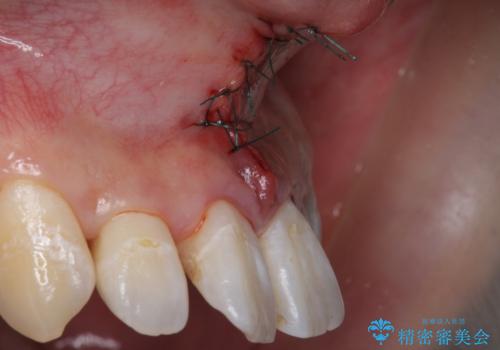

上唇小帯の切除

- 矯正治療の検査時に上唇小帯が短いことがわかり、矯正後の後戻りの予防目的で上唇小帯の切除を行いました。

上の前歯の歯と歯の間にすき間がある場合は、上唇小帯のついている位置やその長さが原因となっている場合があります。

そのままにしておくと矯正中に前歯のすき間が閉じきらなかったり、閉じたとしても後戻りをしてまたすき間ができてしまう可能性があります。

矯正の予定がなくとも、上唇小帯のつく位置が歯に近いと清掃性が悪くなるため手術で改善することをおすすめします。

- 外科手術のため、術後に出血、痛みや腫れ、違和感を伴います